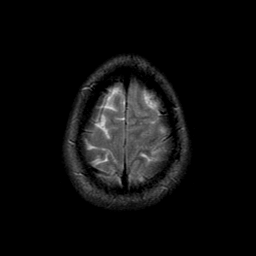

Sarcoma, MR Study #1 mr-t2 -- Slice #22

[Home][Help][Clinical] Slice 22